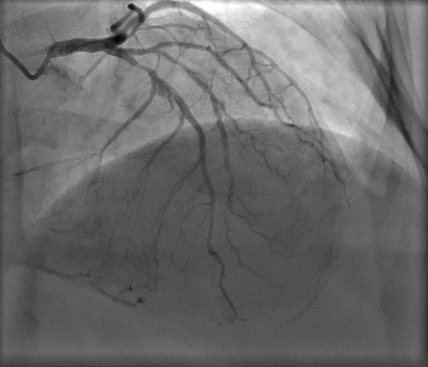

NYHA II dyspnoea on a background of known IHD.

Unstable angina and NSTEMI in August and October 2020. Discussed at that time in the Cardiac MDT meeting. The consensus at that time was for medical therapy due to her comorbidities.

Unstable angina again with 2 x admissions since October and most recent admission with NSTEMI (Trop 100).

- What are the indications for the surgical treatment in this patient? What are the confounding medical and social issues for this patient in consideration of management of her IHD?

- The patient is accepted for CABG after the cardiac MDT. What is your operative plan for conduit and justification in this patient?